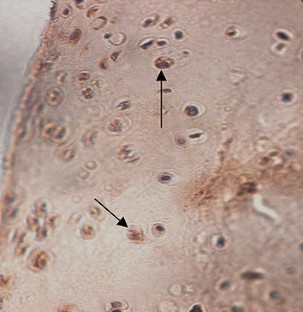

Observe pulse electromagnetic fields (PEMFs) effects on ovariectomized (OVX) rats, to study the mechanisms of PEMFs therapy for postmenopausal osteoarthritis. Forty-eight female rats were exposed to PEMFs (PEMFs group), administrated E2 and placebo PEMFs (E group), or were treated with placebo PEMFs (OVX and Sham groups). The treatment duration was 30 days after which serum E2 levels, chondrocyte morphology, chondrocyte apoptosis and matrix metalloproteinases-13 expression in knee joint was analyzed. We observed differential chondrocyte formation in each group, and serum E2 content in the PEMFs and E group were significantly higher than the OVX group. The apoptosis index of chondrocytes and the positive index of MMP13 expression in the PEMFs group and E group were significantly lower than the OVX group. PEMFs has a systemic effect on estrogen metabolism in ovariectomized rats, then inhibit chondrocyte apoptosis and downregulate MMP13 expression of knee joint cartilage. It may be the mechanisms by which PEMFs therapy works for on postmenopausal osteoarthritis.

Fig. 1

Fig. 2

Fig. 3

Fig. 4

Fig. 5

Fig. 6

Fig. 7

Fig. 8

Fig. 9

Fig. 10

Fig. 11

Fig. 12